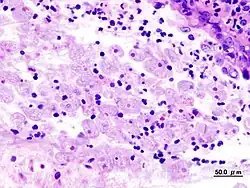

Trofozoítos de Entamoeba histolytica con eritrocitos digeridos en preparación de heces | ||